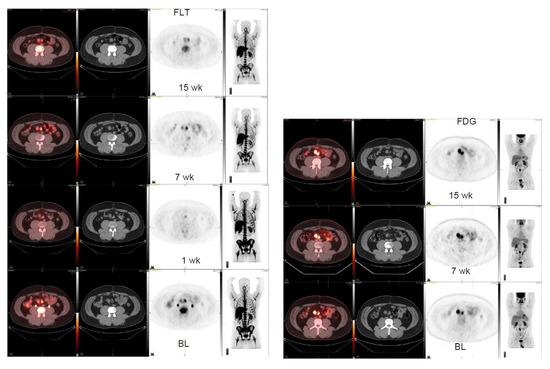

| 50/F | Liposarcoma, anterior peritoneal mass | 5.8 2.6 × 1.8 | 4.2 2.0 × 1.7 8 weeks | 3.5 1.7 × 7.1 15 weeks | Big tumor change 3.2 × 4.1→4.1 × 5.5→ 5.2 × 5.6 | −28% |

| 32/ M | GNET, mesenteric lnn R | 5.2 2.2 × 1.9 12.9 | 3.9 2.0 × 2.0 15.4 7 weeks | 2.8 1.9 × 1.7 10.6 15 weeks | 3.2 (1 week) 2.0 × 1.8 (1 week) FDG | −25%+19% |

| 32/ M | GNET, mesenteric lnn L | 5.5 2.3 × 1.1 8.2 | 5.9 2.1 × 1.4 9.9 7 weeks | 4.0 2.0 × 1.2 8.0 15 weeks | 3.4 (1 week) 1.9 × 1.5 (1 week) FDG | +7% +21% |